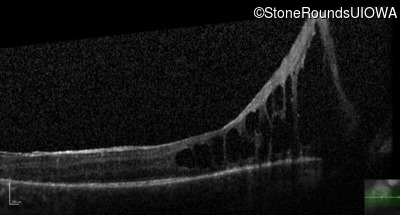

Optical Coherence Tomography - Left - 20/600 sc

Exemplar / OCT Stack